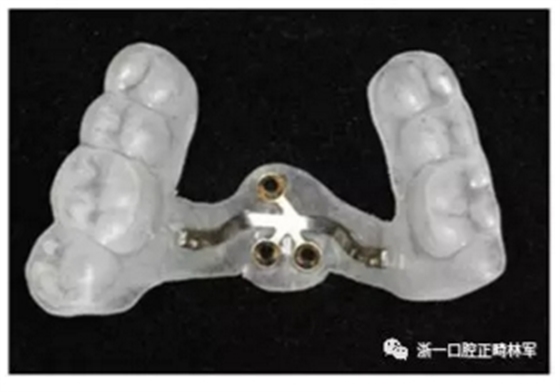

上頜使用3顆微種植釘(2x8mm)固定改良腭板作為骨支抗。安裝過程如下圖所示。